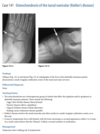

61yr old woman with shoulder pain

AP Radiograph of left shoulder in external and internal rotation (1 & 2) - globular foci of calcification in expected location of supraspinatus (White arrow) and infraspinatus (black arrow) and pectorals major

DIAGNOSIS: Hydroxyapatite deposition disease

(HADD)

HADD consists of crystal deposition in

and around joints, without a known cause.

AKA calcific tendonitis

On radiographs, the calcium deposits appear cloud-

like and amorphous and can involve the tendon,

ligament, bursa, or joint capsule. Intraarticular crys-

tal deposition can destroy the joint space, resulting

in a condition referred to as “Milwaukee shoulder.”

On CT,

­ accompanying erosion of the underlying bone can be

seen. CT appearance has been described as commonly

having a flame-shaped or comet-tail configuration of

the calcifications

If not in shoulder/region not common for HADD ?Malignancy